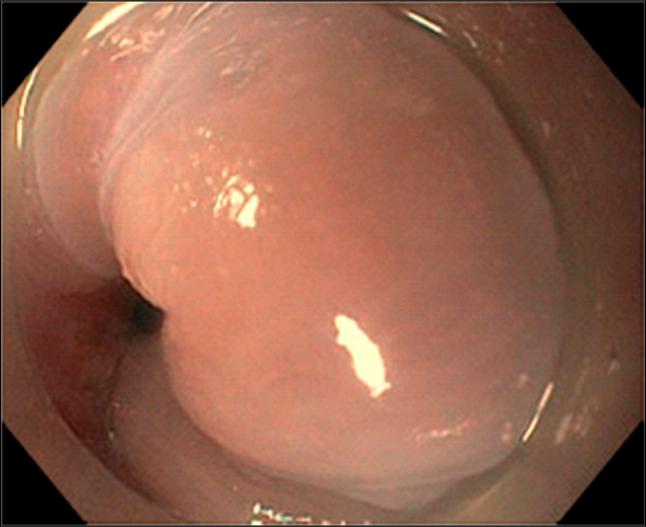

The concomitant presence of esophageal achalasia and esophagogastric junction submucosal leiomyoma is extremely rare. Peroral endoscopic myotomy has been endorsed as one of the primary interventions to manage esophageal achalasia. We present a 49-year-old woman who had initial endoscopic evaluation and diagnosis of achalasia type II then underwent peroral endoscopic myotomy and found to have incidental submucosal leiomyoma at 1 cm distal to esophagogastric junction. It was removed successfully by submucosal tunneling endoscopic resection. This poses the question of whether this is a case of achalasia or pseudoachalasia caused by leiomyoma.

食管贲门失弛缓症与食管胃交界黏膜下平滑肌瘤同时存在极为罕见。经口内镜下肌切开术已被认可为治疗食管贲门失弛缓症的主要干预措施之一。我们报告一名49岁女性,最初经内镜评估诊断为Ⅱ型失弛缓症,随后接受经口内镜下肌切开术,结果发现在食管胃交界远端1 cm处有偶然发现的黏膜下平滑肌瘤。通过黏膜下隧道内镜切除术成功将其切除。这就引发了一个问题,即这是一例由平滑肌瘤引起的失弛缓症还是假性失弛缓症。